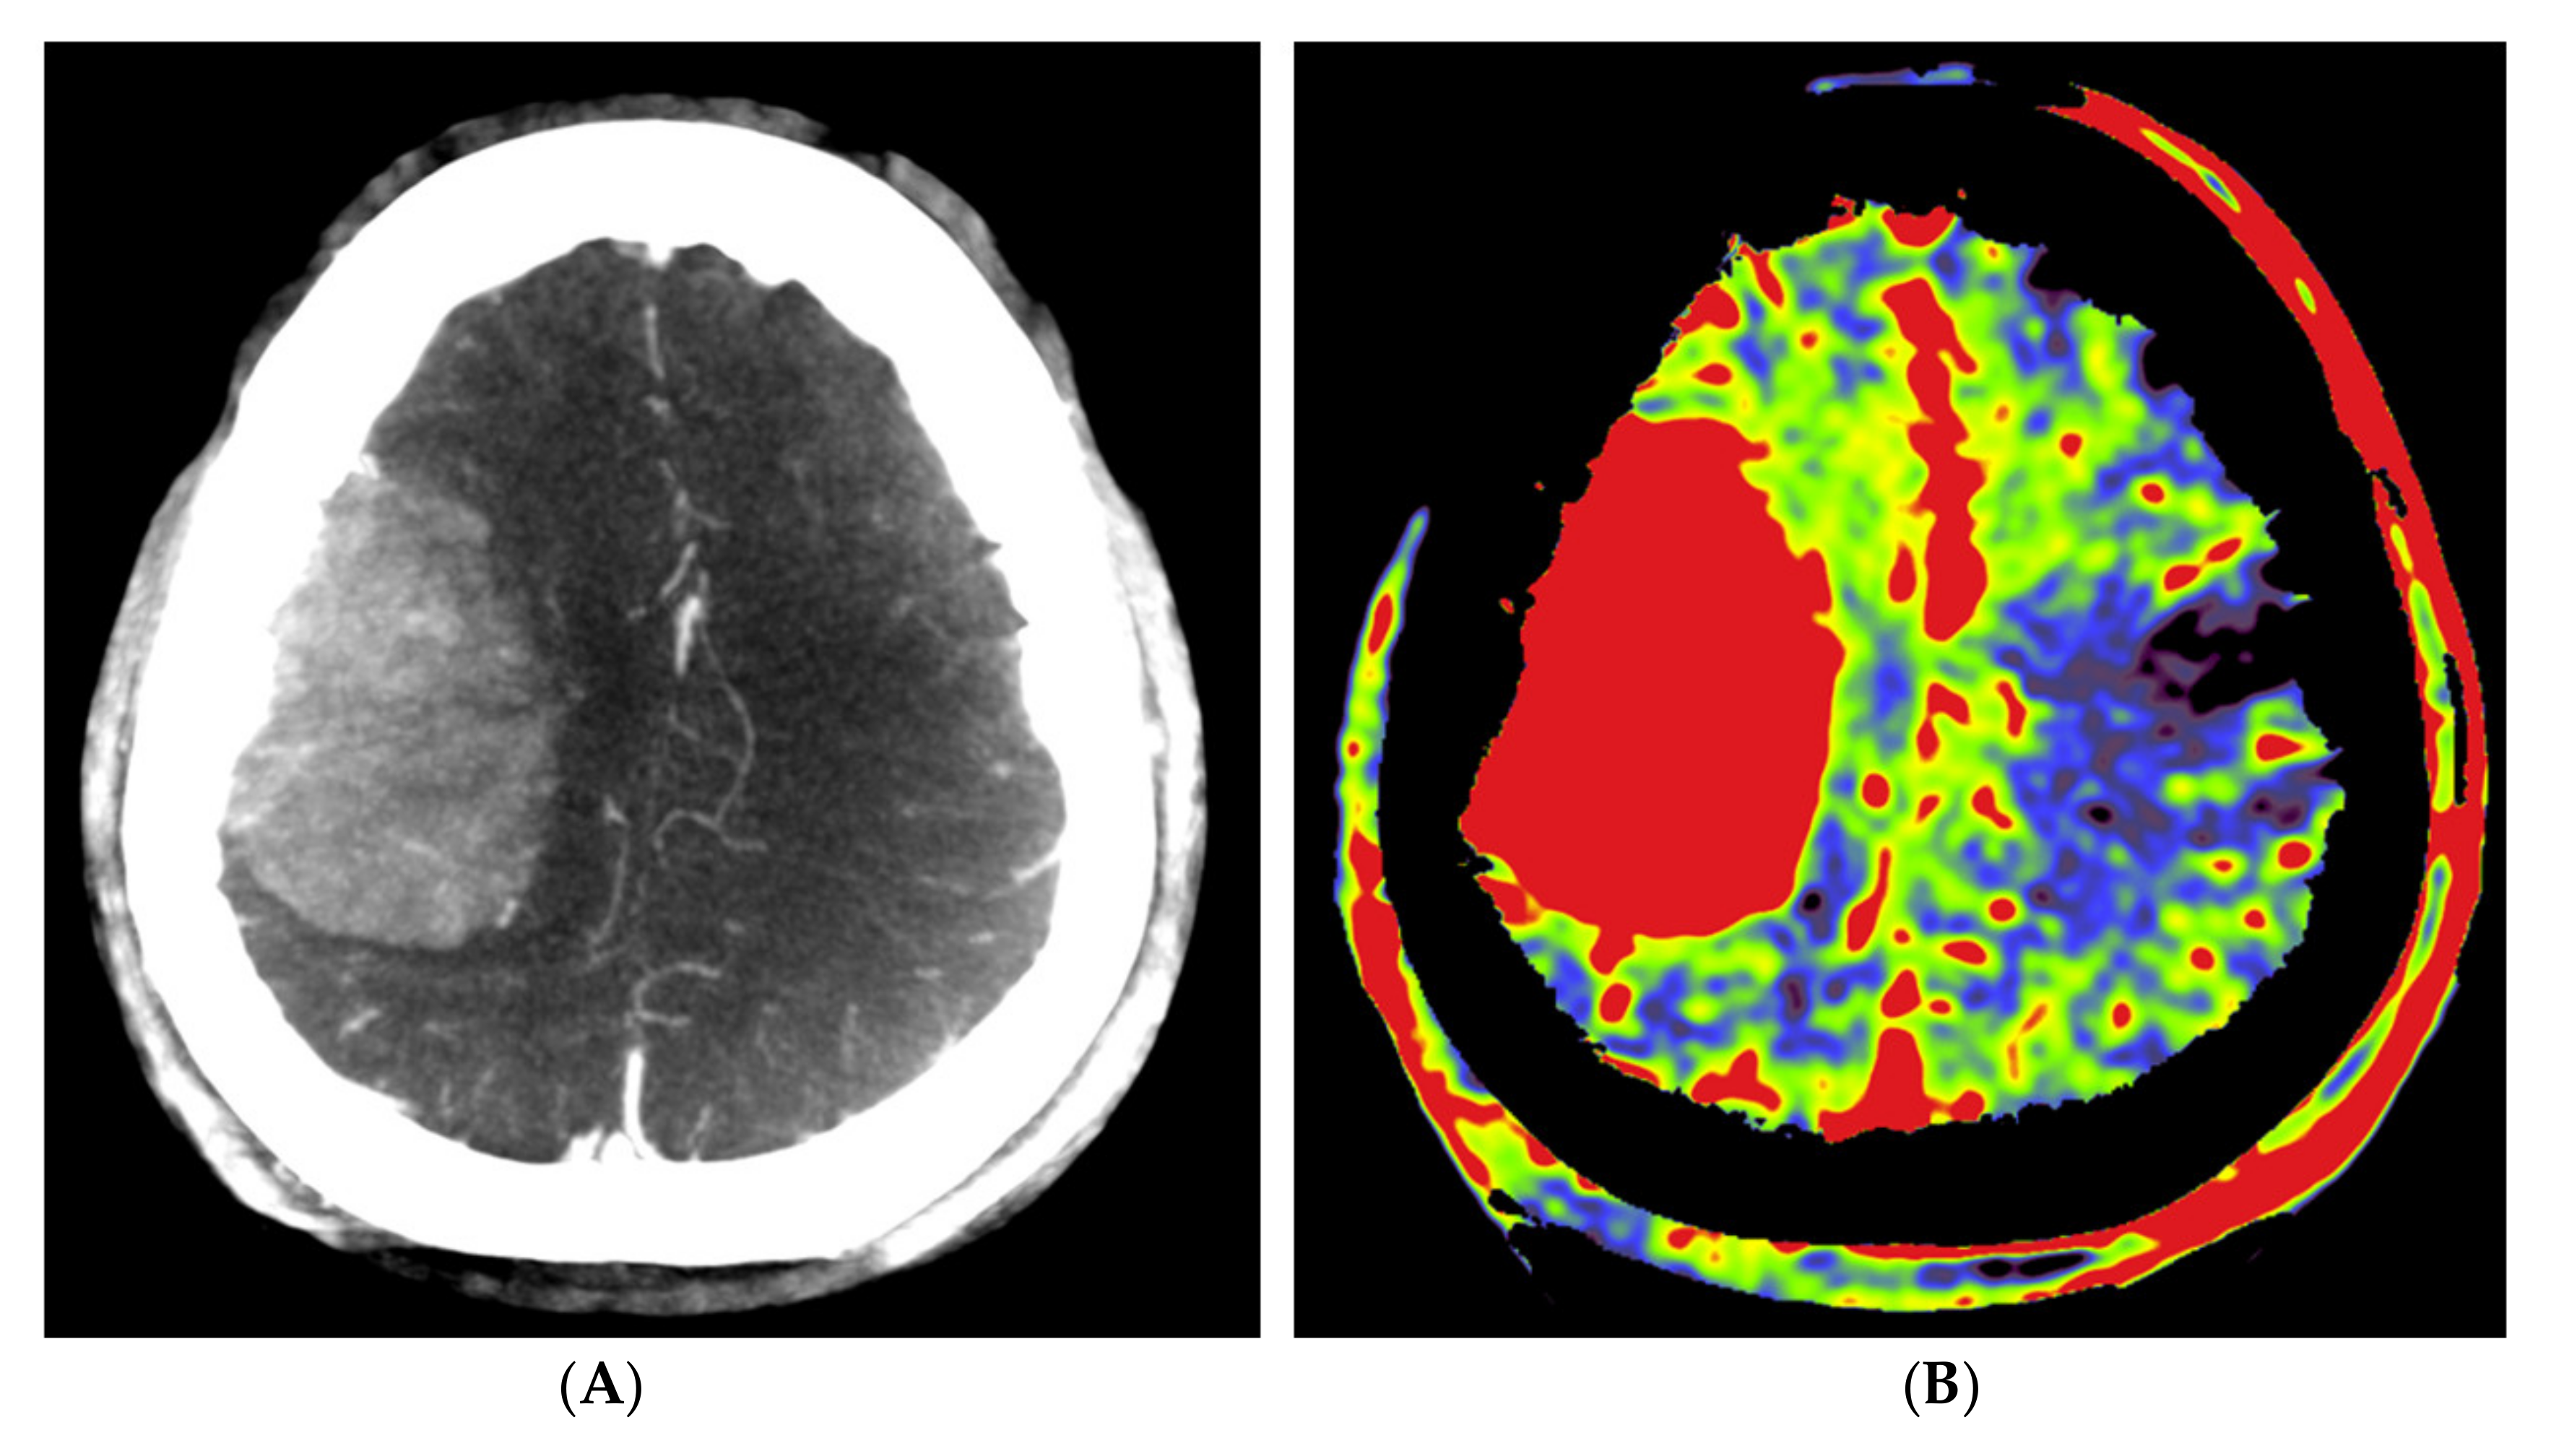

The angiographic PBV perfusion acquisitions were technically successful in all our patients. No adverse events occurred during the angiographic examinations or during or after the embolization procedures. In all patients, a mixed pial and dural vascular supply pattern was present. Figure 2 shows an example of the PBV images obtained after selective and aortic arch injections pre- and post-embolization, respectively.

Figure 2.

Imaging of a patient with a right-sided perisylvian meningioma. (A) Axial post-contrast T1-weighted MRI image of patient no. 4 shows the presence of an enhancing, extra-axially located tumor in the right perisylvian area. (B) Pre-embolization axial PBV reformation obtained after selective right external carotid artery injection and (C) after aortic root contrast injection shows a hypervascular tumor. In consultation with the operating neurosurgeon, a pre-operative embolization was performed. (D) Post-embolization axial reformation of whole brain PBV scan shows devascularization of the portion supplied by the dural feeder.